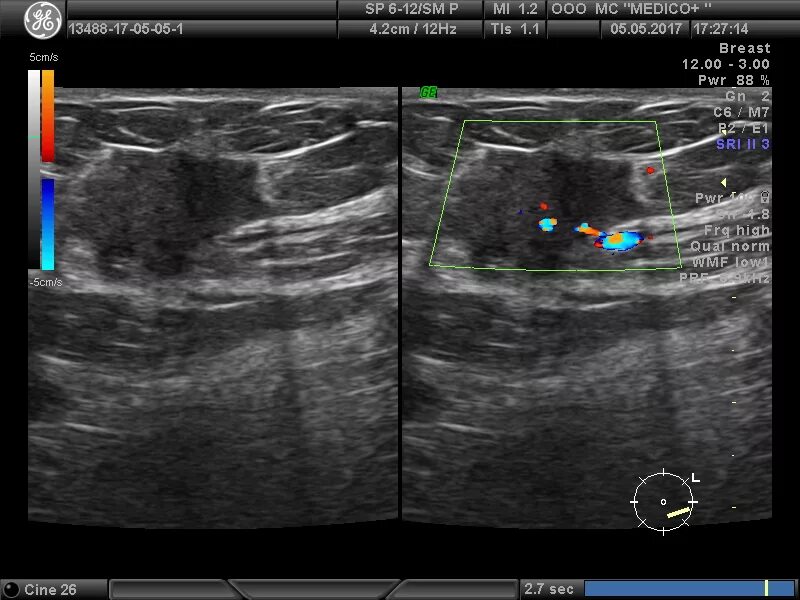

Локусы при цдк что это